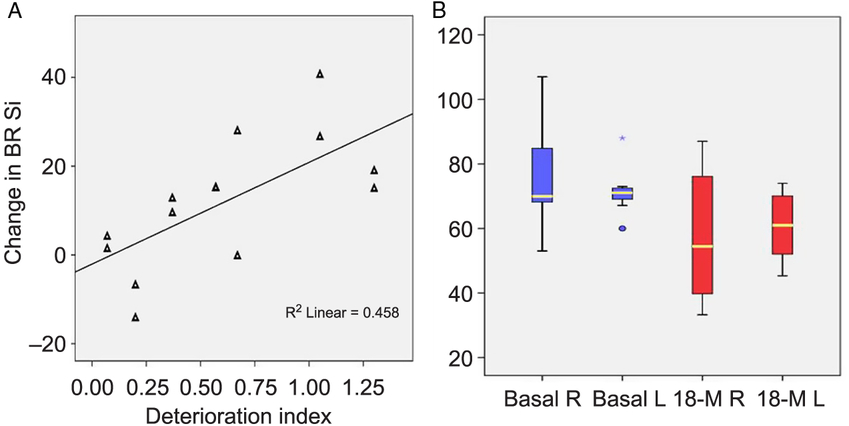

Two patients from the original cohort were further excluded for having another diagnosis, 6 subjects died during the time interval, 8 did not present themselves to the programed MRI, and 12 were dispensed due to poor tolerance of the dorsal decubitus or the use of respiratory device. Seven patients underwent a second study at 18 months follow-up. All subjects exhibited changes in BR signal intensity and area when compared with the first visit (Figure 5). Signal intensity was the most objective and sensitive variable for estimating the changes in the BR paramagnetic effect over the 18-month interval. A multivariate analysis indicated a significant change of 12 AUSI between the first and second MRI studies (F = 6.96, p = 0.014) (Figure 6B). The joint measurements of both hemispheres, before and after the 18-month interval, showed an even more significant difference from the mean values of 68.5 to 49 AUSI, 95%CI: 61.4–75.6 to 37.9–60.1 (p = 0.004). Interestingly, this difference in intensity corresponding to the elapsed period in each BR is related to the rate of deterioration of patients (rho coefficient = 0.677; r 2 = 0.458; p = 0.008) (Figure 6A). This correlation is even more important than that of Kimura’s index of deterioration with the intensities of all the initial BRs (Pearson correlation: −0.299; p = 0.053) despite the small sample of patients followed for 1 year and a half.

Figure 6: Changes in signal intensity after 18 months. (A) Changes are significantly correlated with the deterioration index on the left figure (p = 0.008). (B) Right and left signal intensity measurements in BR at inclusion and after 18 months. A multivariable analysis detected significant changes between the time points (f = 6.96, p = 0.014).